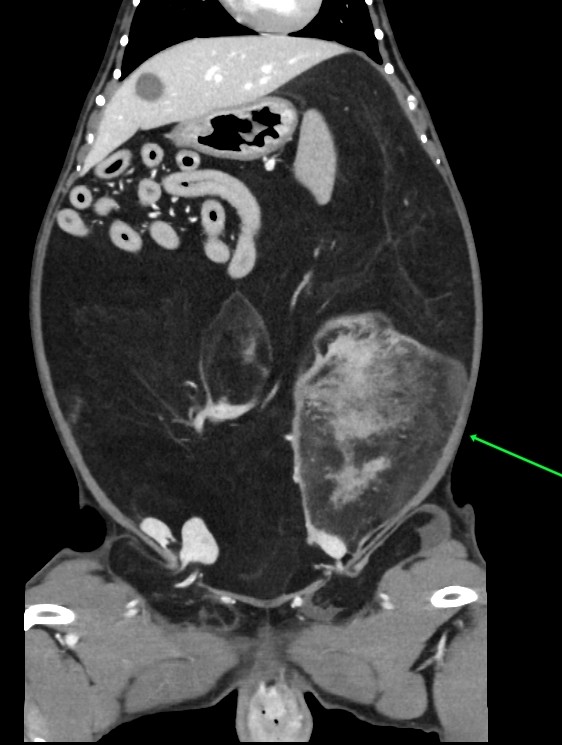

CTでは、大きな脂肪の塊らしきものが複数

特に矢印の白いのが固い脂肪の疑い

その周囲の黒いのが軟らかい脂肪

お腹の中は3/4が脂肪に置き換わっていそうです